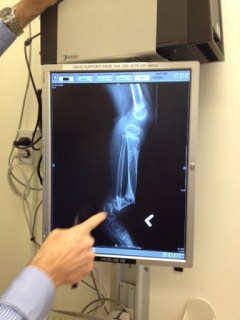

Here it is. Branko’s left leg. And don’t even get me started on the right one. If you look very carefully, you might notice that his tibia (biggest bone) is not quite lined up with the ankle. In fact, the bottom of the tibia is nearly poking out of his skin.

What we thought was a minor bone deformity (he was diagnosed with a mysterious genetic bone disease; more on that later) turned into something much worse as he grew and got a bit older. Quite simply, the bones aren’t growing properly. Perhaps they are weaker than normal; perhaps they are normal and, for whatever reason, they never quite lined up properly. Perhaps he will have to have multiple, repetitive surgeries until he stops growing. Perhaps he won’t. Perhaps he will need leg braces for years to come; perhaps he will walk comfortably without them. One thing I do know: not knowing anything about his future sucks. As parents of a child with the aforementioned mysterious bone condition, we don’t know anything. Squat. Diddly. Nothing. Every doctor has told us to “Prepare for the worst, hope for the best.” The doctors want to help him. They want to help and comfort us. But they simply don’t know what to say. He is, quite literally, the only person so far on this planet with this condition. (Lucky us?) They don’t want to give us false hope. I don’t really blame them.